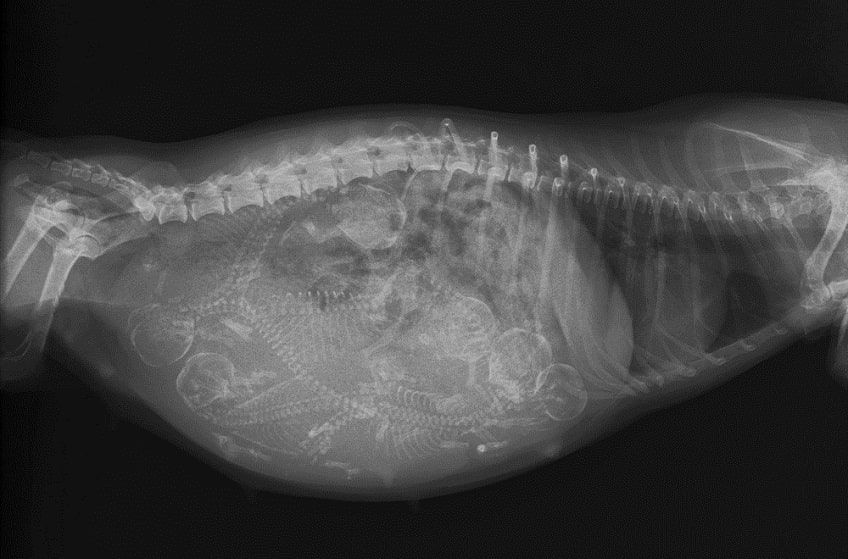

Wielkość miotu można określić za pomocą badania RTG w 7. tygodniu ciąży. Na zdjęciu widoczne będą już czaszki i kręgosłupy maluchów. Badanie USG pozwoli natomiast ocenić, czy rozwój narządów wewnętrznych płodu przebiega prawidłowo.